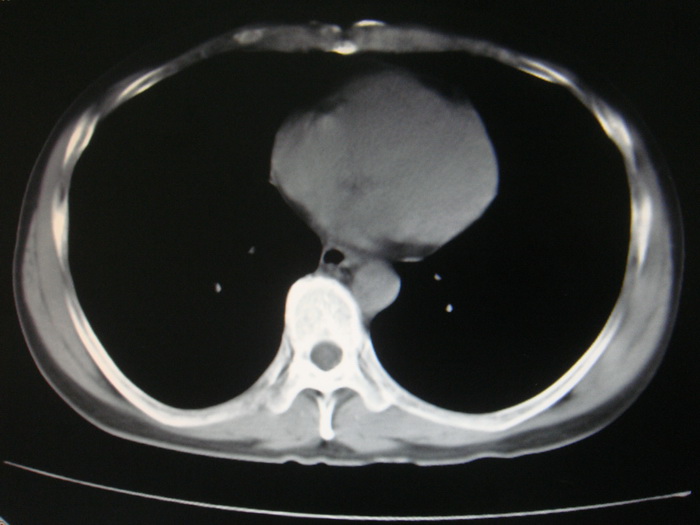

标题: CT28366:男性,45岁,偶尔发现右颈部肿块行胸部CT扫描。 [打印本页]

男性,45岁,偶尔发现右颈部肿块行胸部ct扫描。

两肺多发结节灶及纵膈淋巴结肿大考虑为转移

两肺多发性转移瘤,纵隔淋巴结转移。

两肺多发性转移瘤,纵隔淋巴结转移。食道中上段管壁似乎增厚,作相关检查。

颈部肿块也可能是转移。